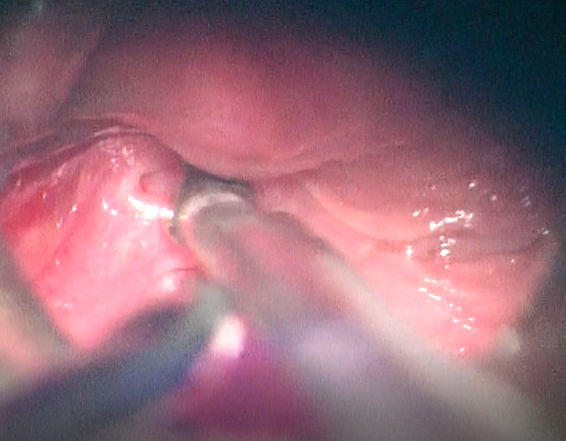

Figure 1: Orifice of the

fistula in the left piriform fossa in endoscopic view

The second clinical case is a 6

years old child admitted with a left latero-cervical tumefaction presenting a

history of recurrent superinfection. A hypopharyngoscopy was performed on the

suspicion of a 3rd or 4th cleft fistula, revealing the presence of a fistulous

orifice at the bottom of the left sinus prirforme. The both patients underwent

cauterization with very good post-operative improvement, nine months after surgery, there were no signs of

neck infection or purulent episodes.